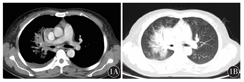

例1,女性,44岁,因间断发热3年,咳嗽、胸闷20 d,于2013年7月26日入院。患者入院前间断发热3年,体温最高39 ℃,伴咳嗽,给予抗生素及激素治疗后间断好转。逐渐出现发热、咳嗽、咳痰加重及胸闷、体质量下降等,行抗生素治疗效果差,CT检查发现右肺占位,考虑结核,在结核病医院行结核相关检查为阴性,支气管镜检查为阴性。再次行胸部CT检查,右肺上叶占位,肺癌可能性大;右肺下叶影像学改变考虑肺炎,右侧少量胸腔积液,以右肺占位待查(肺癌可能性大)收入院。入院查体:一般情况好,全身皮肤黏膜无黄染及皮下出血点,浅表淋巴结未触及,左肺呼吸音清,右肺呼吸音低,心率90次/min,律齐,各瓣膜听诊区无杂音。肝脾肋缘下未触及。入院后实验室检查,血常规:白细胞计数(WBC) 2.8×109/L,血红蛋白(Hb) 94 g/L,血小板计数(Plt) 211×109/L,血β2微球蛋白3.7 mg/L,乳酸脱氢酶(LDH) 469 U/L,清蛋白27 g/L。患者发热,体温40 ℃,给予左氧氟沙星联合头孢曲松抗感染治疗无效;多次痰培养及血培养均未见细菌生长,给予降钙素原0.16 ng/ml治疗,换用哌拉西林钠他唑巴坦钠联合丁胺卡那抗感染治疗,效果仍然差。同时行支气管镜检查:右肺小细胞癌待排除。免疫组织化学:LCA+、Ki-67+ 80 %、Vim+、CK-、CK5/6-、CK7-、SCLC-、CD56-、Syn-、CD20-、CD3+、CD79a-、CD43+、CD4+、CD5灶阳性、MUM-1-、CD10-、bcl-6-,CD30-、ALK-、TdT-,提示:非特异性T细胞性非霍奇金淋巴瘤。骨髓穿刺:增生活跃,粒系占0.815,胞质颗粒增多、增粗。腹部B型超声未见异常,双颈部、腋窝、腹股沟B型超声均未见肿大淋巴结。我院胸部CT检查示:右肺上叶近肺门一不规则软组织影,边界不清,支气管狭窄,内可见支气管气相,右肺门纵隔内可见淋巴结,部分钙化(图1)。明确诊断为:原发性肺PTCL-NOS。行GLD方案(吉西他滨+奥沙利铂+地塞米松)化疗1个疗程,体温仍然控制不佳。再次行胸部CT示:右肺病灶较前增大。考虑患者肿瘤恶性度高,建议更换化疗方案,家属拒绝继续化疗。患者持续高热伴胸闷气促,给予对症处理,于1个月后因呼吸衰竭死亡。

1A:纵隔窗,右肺上叶近肺门一不规则软组织影;1B:肺窗,右肺上叶软组织影,内可见支气管气相,边界不清,支气管狭窄,右肺门纵隔内可见淋巴结,部分钙化